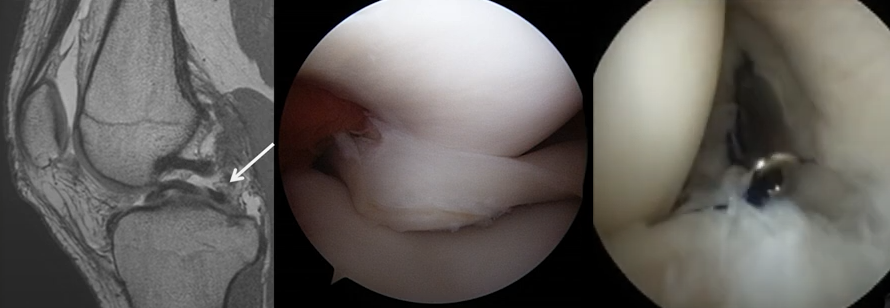

이러한 퇴행성 원인 외에도, 회전력이나 강한 충격량으로 (운동선수) 찢어지기 쉽습니다. 다른 조직들과 달리, 회복이 어려운 편이며 찢어짐과 동시에 관절운동에 방해가 되기 시작하면 무릎이 걸리는 느낌 혹은 통증까지 나타날 수 있습니다.

아래와 같이 다양한 형태로 찢어질 수 있으며, 치료를 하지 않고 방치하는 경우 상당히 진행할 수 있습니다.